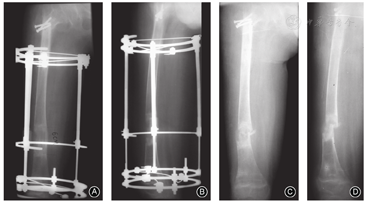

是指在拆除延长器数月后,患肢在无明显暴力的情况下发生的骨折(图5)。一般发生在延长骨段或新骨与原始骨接合处,主要原因为骨愈合强度未达标准、未实施分期拔针拆除、早期功能训练未提供支具保护等[8]。

Paley等[7]将并发症分为问题(problem)、障碍(obstacle)和并发症(complication)三大类。问题是指延长过程中出现的问题,不需要手术即能完全解决;障碍是需要再次手术才能完全或基本解决的问题;并发症是指延长期间或治疗结束后,一直受影响且通过再次手术未能完全解决的局部或全身问题,最终遗留不同程度的后遗症(图6)。在肢体延长过程中延长部位、延长幅度、延长速度以及患者体质、年龄等均与并发症的发生息息相关。一般说来,大腿软组织丰厚、肌力强大,更易发生并发症。文献报道在91.5%的下肢延长病例中,当延长至肢体长度的15%时,能获得良好的结果,即使出现某些并发症,也对最终结果无影响;当肢体延长超过肢体长度的20%时,问题和障碍往往会转化为并发症,即随着肢体长度的增加,某些并发症的数量和严重程度也在增加[32]。具体到每种情况还有一些特殊的限定,不再赘述。